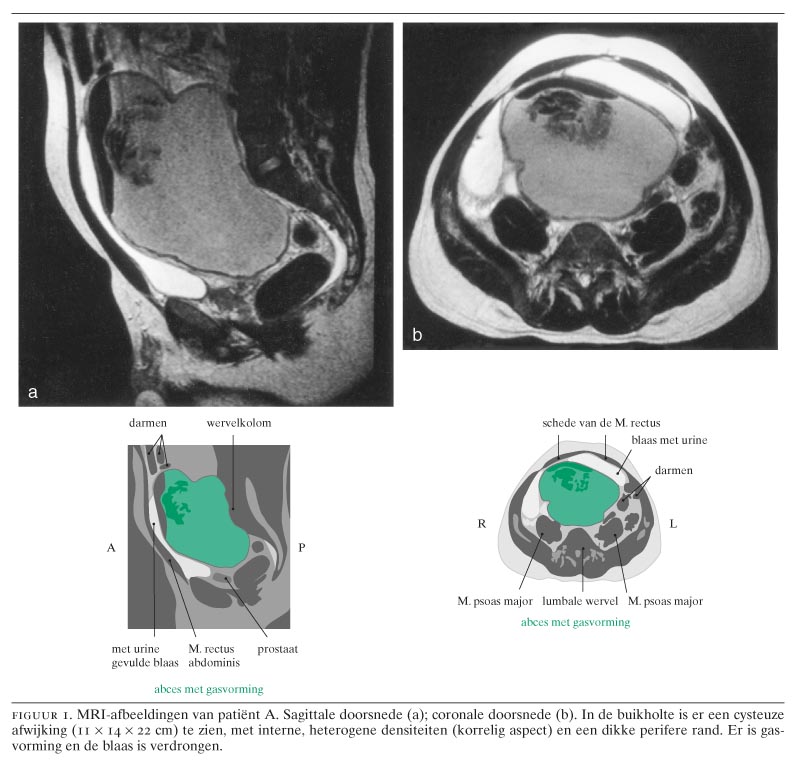

Patiënt C, een 41-jarige vrouw, onderging een abdominale uterusextirpatie in verband met een uterus myomatosus. De operatie verliep zonder problemen en na tien dagen kon zij worden ontslagen. Tijdens de opname maakte zij een koortsepisode door, die werd toegeschreven aan een cystitis, waarvoor zij kortdurend een antibioticakuur kreeg. Drie weken later kwam zij ter controle op de polikliniek. Hierbij klaagde zij over algehele malaise, buikpijn en gallig braken. Bij lichamelijk onderzoek was een zwelling suprapubisch palpabel. Gedacht werd aan urineretentie, maar dit kon via katheterisatie niet worden aangetoond. Vervolgens werd een buikoverzichtsfoto gemaakt, waarop de contouren van een buikrol werden gezien (een buikrol is een groot opgerold gaas dat er tijdens de operatie toe dient het darmpakket buiten het operatiegebied te houden) (figuur 3). Patiënte werd overgeplaatst naar de afdeling Heelkunde van ons ziekenhuis. Dezelfde dag werd een laparotomie verricht, waarbij de buikrol werd verwijderd en de buik gespoeld. Het postoperatieve beloop was ongestoord.

Sinds de jaren zeventig van de vorige eeuw wordt in Nederland in voor operaties bedoelde gazen een looddraad aangebracht, zodat deze op een röntgenfoto aantoonbaar zijn. Vóór die tijd was een gaas niet op een routineröntgenfoto zichtbaar. Vanwege kostenbesparing worden bij poliklinische verrichtingen vaak gazen zonder looddraad gebruikt, zowel bij kleine ingrepen als bij het verbinden of opvullen van soms diepe wonden. In sommige andere landen worden ook nog steeds gazen zonder looddraad gebruikt.

Ondanks alle voorzorgsmaatregelen komt het, zoals ook bij de door ons beschreven patiënten, nog steeds voor dat onbedoeld medisch hulpmateriaal in het operatiegebied achterblijft. Hiervoor bestaat een aantal oorzaken, zoals het gebruik van vele gazen, wisselingen van operatiepersoneel bij langdurige ingrepen en menselijke omissies. Andere redenen zijn het gebruik en niet-noteren van ongebruikelijke hulpmiddelen, bijvoorbeeld een buikrol (groot verbandgaas), zoals bij patiënt C. Tijdens een abdominale ingreep kunnen 1 à 2 buikrollen gebruikt worden om het dunnedarmpakket terzijde te houden. Juist de vanzelfsprekendheid dat een buikgaas niet vergeten zou kunnen of mogen worden, kan leiden tot het blinde vertrouwen dat de buikrol aan het eind van de operatie uit de buikholte verwijderd is. Evenzo is dit mogelijk bij kleine en oppervlakkige ingrepen, waarbij het risico op het achterlaten van een gaas onmogelijk lijkt (zie patiënt B).